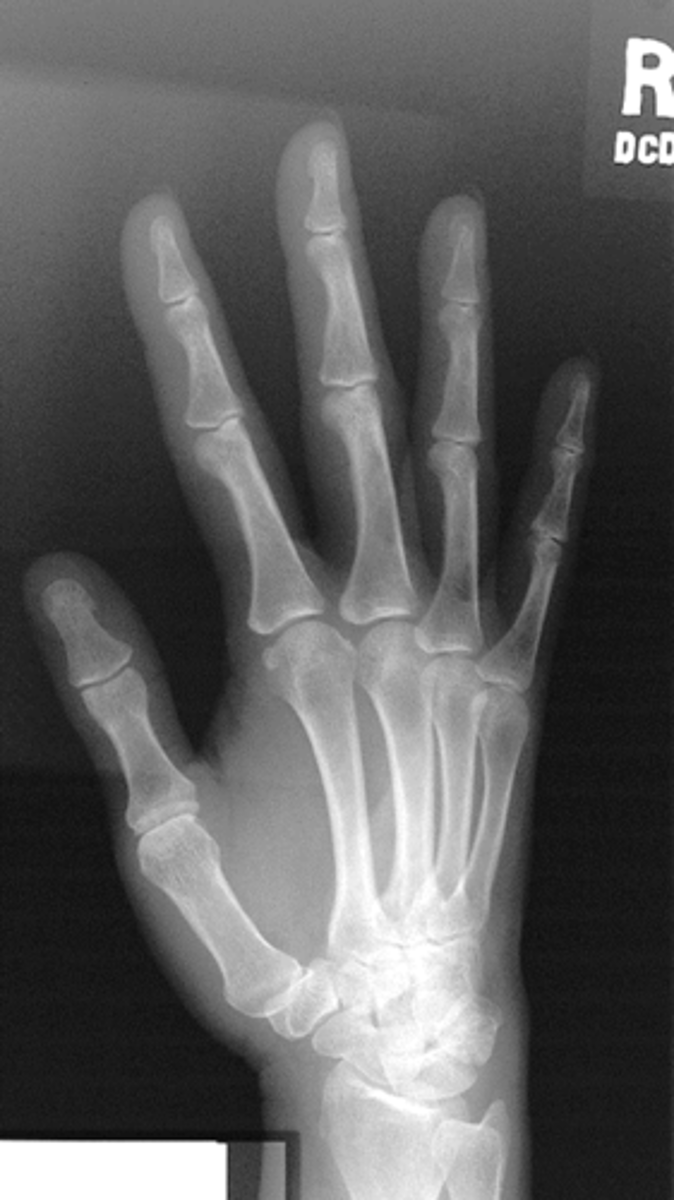

PA oblique hand